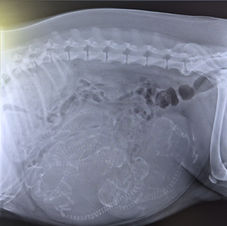

Wurf-Tagebuch